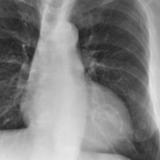

Calc Ao valve & LtA

Date: 01/26/2009

Views: 3000